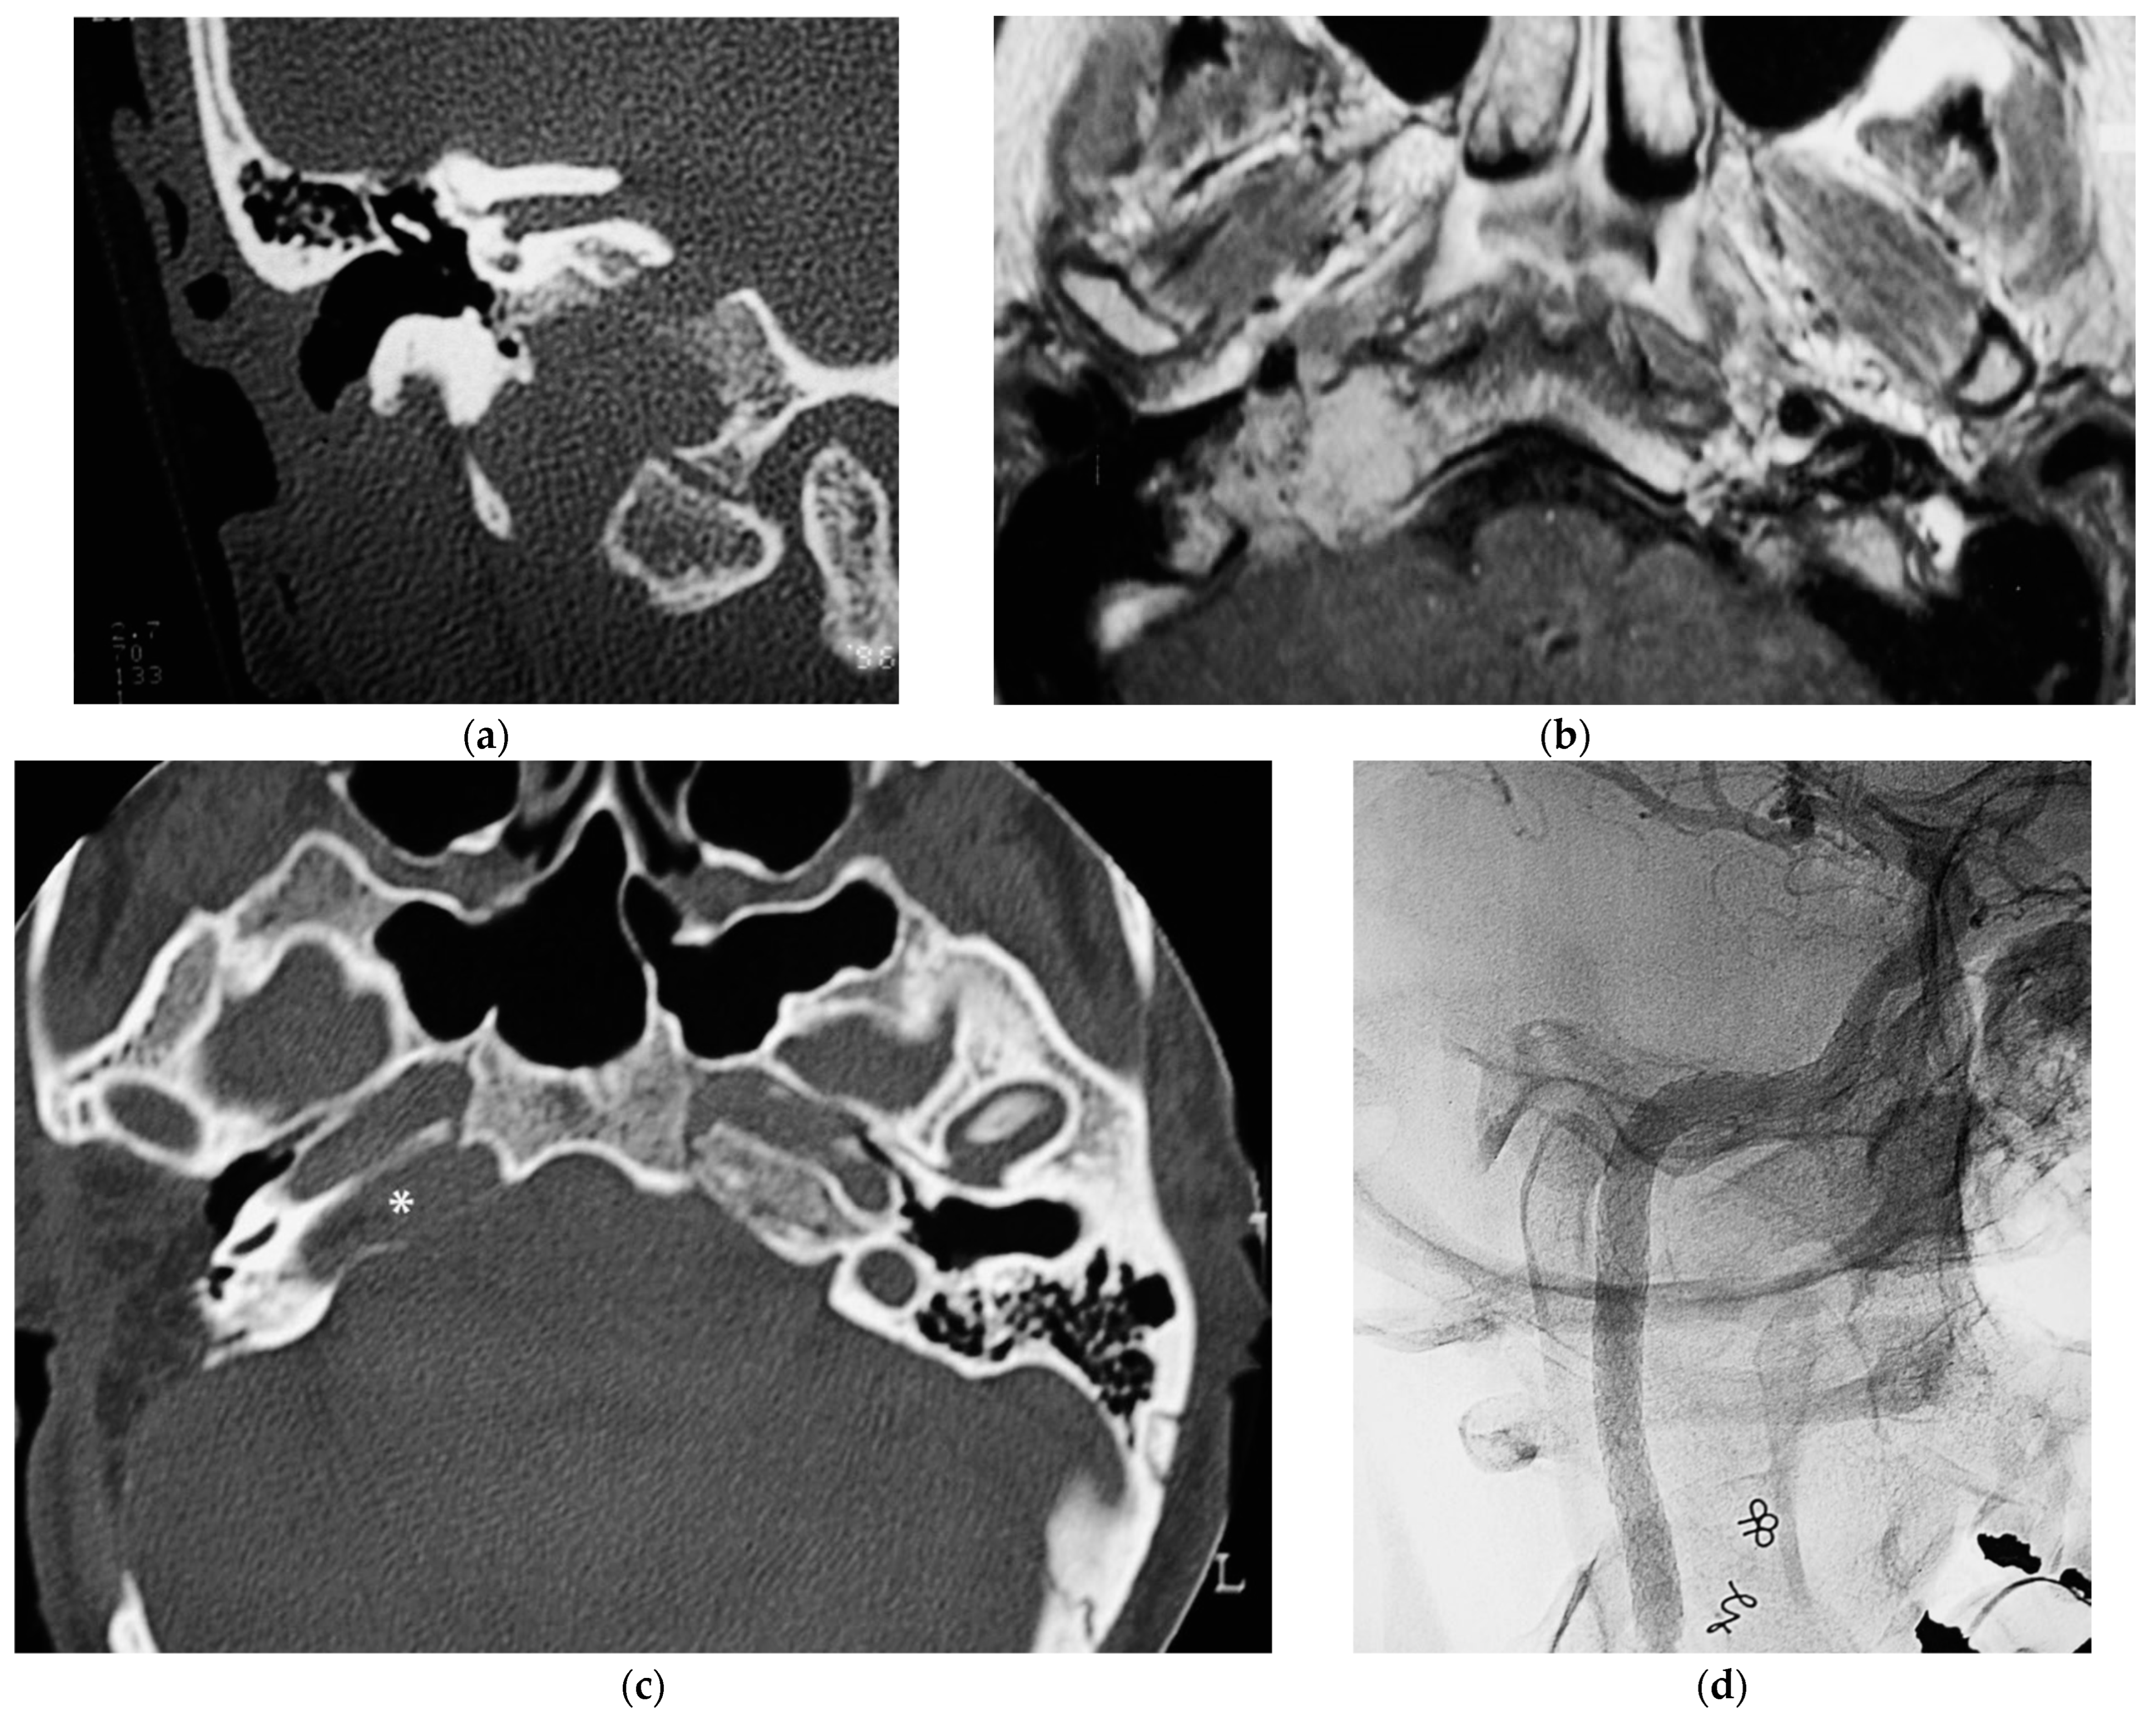

5.4. Case 4: (C3Di2 + Stage II Vagal PGL)

5.5. Case 5: (C3Di2Vi)

5.6. Case 6: (C4Di2Vi)